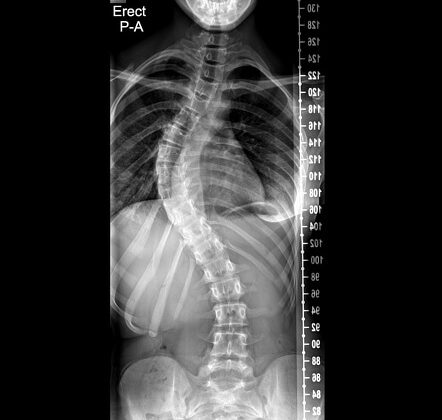

يعاني بعض الأطفال والمراهقين من اعوجاج العمود الفقري، وهو انحناء جانبي غير طبيعي للعمود الفقري يظهر خلال فترة النمو. وفي حالات كثيرة، كلما تُرك الانحناء دون علاج لفترة طويلة، يصبح تصحيح العمود الفقري أكثر صعوبة. هذا لأن الجسم يمر بتغيرات حيوية تجعل العمود الفقري “عالقًا” في وضعه المنحني.

العضلات والأربطة المحيطة بالعمود الفقري تبدأ في القصر والتصلب. هذا يجعل العمود الفقري أقل مرونة، ويزيد صعوبة تصحيحه لاحقًا.عدم تماثل العظام:

مع مرور الوقت، تبدأ الفقرات في التغير بشكل غير متماثل لتتكيف مع الانحناء. تصبح العظام “مشوهة جزئيًا”، وهذا يثقل عملية العودة إلى الوضع الطبيعي.